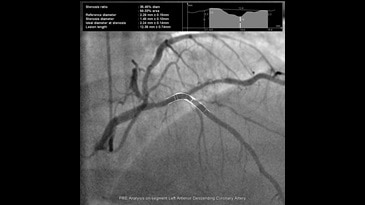

Великолепное качество изображения при низкой дозе

Цифровой квадратный плоскопанельный детектор Revolution имеет уникальную конструкцию, представленную фотодиодной матрицей с аморфным кремнием на монолитной основе без характерных швов. Толщина сцинтиллятора и электронный шум оптимизированы таким образом, чтобы максимально увеличить эффективность использования дозы облучения.

Детектор обладает одним из самых высоких в отрасли коэффициентом квантовой эффективности (DQE). Высокий DQE позволяет получать изображения более высокого качества при применении тех же параметров дозы или изображения прежнего качества при сниженной дозе облучения. Функция Smart Fluoro оптимизирует качество изображения на всех уровнях дозы облучения, обеспечивая возможность использования минимальной дозы облучения при оптимальном качестве изображения.